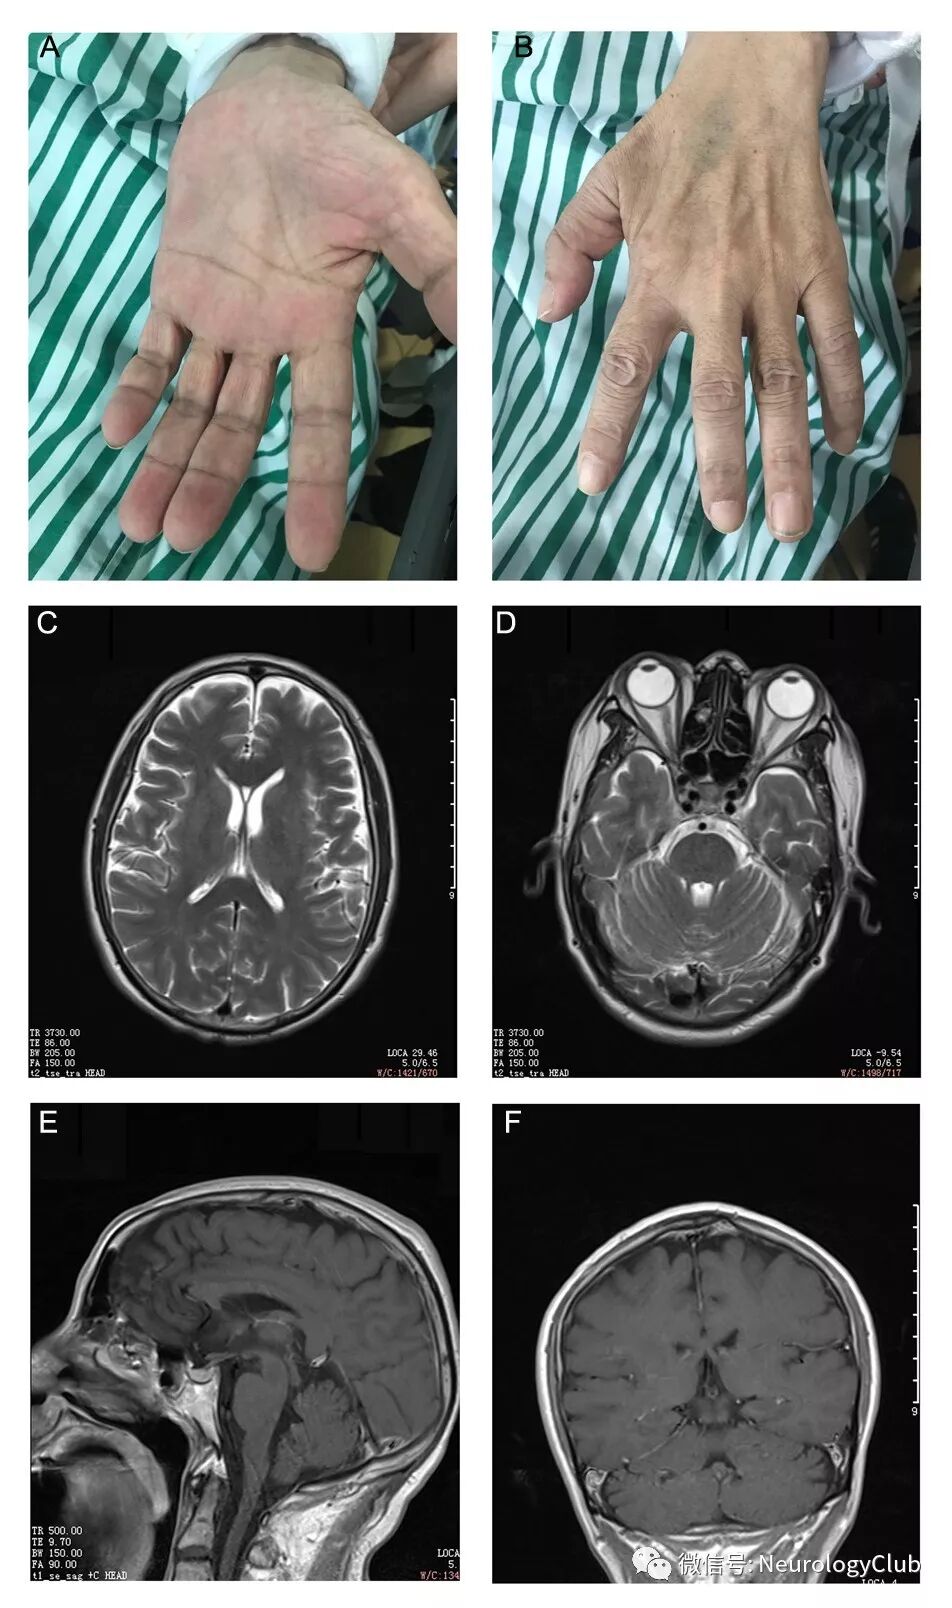

(图:A-B:快速进展性手部肌肉萎缩;C-F:头颅MRI未见明显异常信号或脑萎缩)

入院查体:神志清,精神软,时间、地点、人物定向力可,记忆力、计算力正常,言语稍含糊,双侧瞳孔等大等圆,约3mm,对光反应灵敏,双眼闭合紧,双侧鼻唇沟对称,悬雍垂居中,双侧咽反射消失,伸舌居中,舌肌无明显萎缩颤动,肌力基本正常,双侧颞肌及咬肌轻度萎缩,屈颈肌力IV级,转颈肌力IV级,双侧三角肌及肱二,肱三头肌肌力,远端握力肌力IV级,分指并指肌力差,双侧Hoffman征阴性,双上肢腱反射(++),双上肢近端肌肉容积减小,双侧骨间肌、大小鱼际明显萎缩,双下肢肌力IV级,腹壁反射存在,双下肢腱反射(++),肢体感觉对称存在。指鼻,轮替,跟膝胫试验稳准,双侧巴氏征阴性。

入院辅助检查:血常规,尿常规,粪常规,血生化未见明显异常;血气:PH:7.426,CO2分压:52.9mmHg;O2分压:108.0mmHg;肿瘤指标:CEA 7.1ng/ml;红细胞沉降率、抗核抗体谱、抗中性粒抗体、心磷脂抗体及各项激素水平基本正常。乙肝三系/HIV/ RPR TPPA均阴性。 头颅MRI未见明显异常,脑脊液腰穿压力170mmH2O,脑脊液常规及生化无明显异常,外送血及脑脊液抗体:副肿瘤抗体系列(Hu、Yo、Ri、Amphiphysin、Ma2、CV2、GAD、Titin、Recoverin、PCA-2、ANNA3)阴性;自身免疫抗体系列:脑脊液IgLON5抗体IgG+1:1,血清IgG+++1:320;余阴性(NMDA、AMPA、GABA、LGI 1、CASPR2、DPPX),肌电图:广泛神经源性损害(累及四肢肌、胸锁乳突肌、舌肌、斜方肌、T9椎旁肌,无自发电位,目前腹直肌未累及,双侧第一骨间肌可见大量自发电位),脑电图:轻度异常;睡眠呼吸监测:AHI2.3次/小时,夜间最低血氧饱和度90%,PET-CT:两肺上叶及下叶团片影糖代谢稍增高,考虑炎性病变。HLA-DQB1∗0501 和HLA-DRB1∗ 1001 等位基因检测阳性。